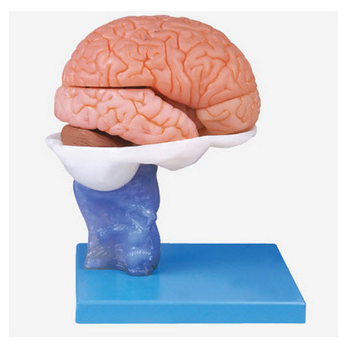

腦解剖模型 GD/A18203功能介紹:■ 該模型由大腦半球、胼胝體、島葉、豆狀核、尾狀核、腦室系統(tǒng)和腦干等15個部件組成,并顯示大腦半球、內(nèi)囊、腦室系統(tǒng)、間腦、小腦和腦干中腦、腦橋、延髓各個部位,以...